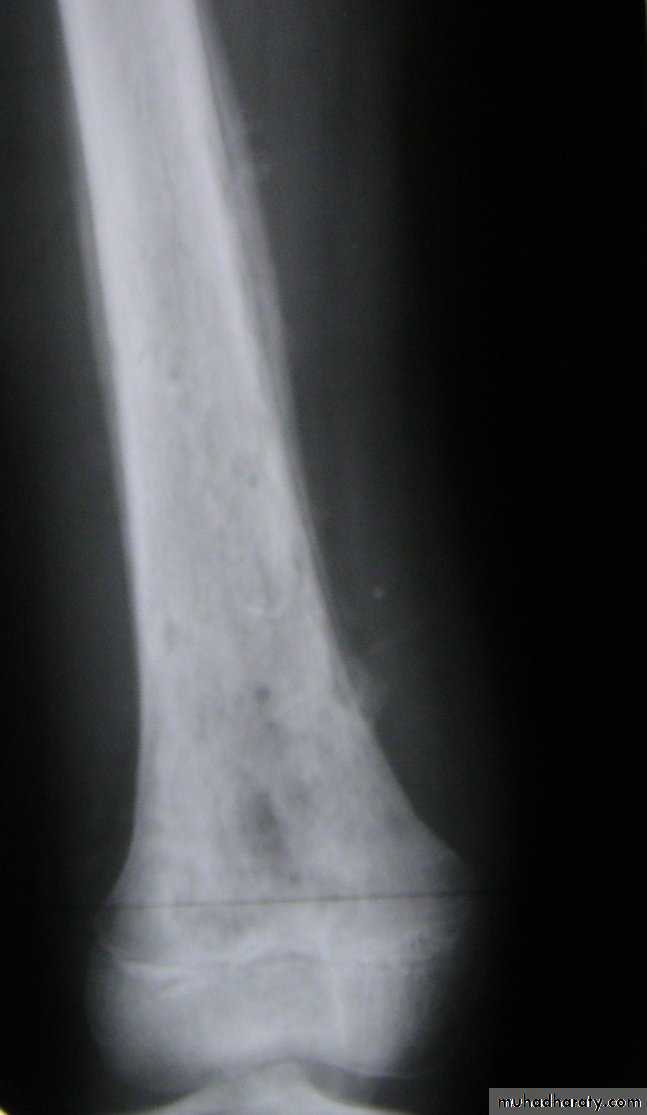

X-ray finding:

x-ray films are negative within 1-2 weeks,Although carefully comparison with the opposite side may show abnormal soft tissue shadows.

It must be stressed that x-ray appearances are normal in the acute phase. There are little value in making the early diagnosis.

Radiography not appear till after 3 weeks.

decrease bone density moth eaten.later on new bone formation.